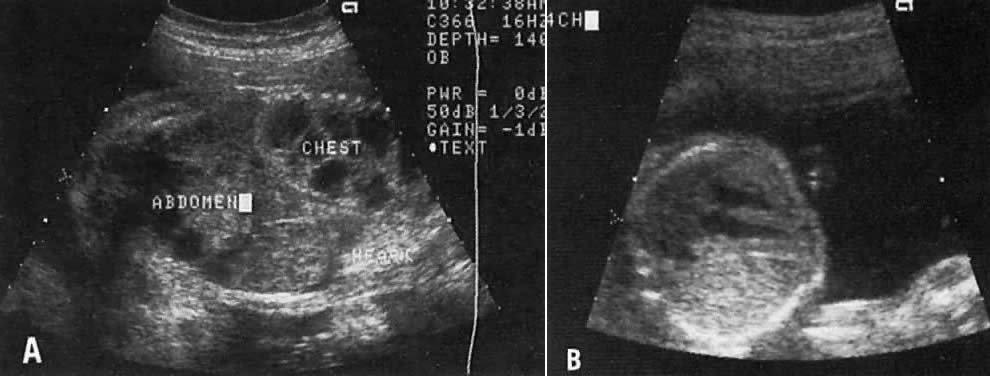

Type I: The cysts are large ( 2 cm). The prognosis depends on the size of the tumor and the degree of fetal hydrops (Fig. 10). If the fetus survives, resection of the affected portion of the lung is usually indicated.

Fig. 10. A. Longitudinal echogram of fetus with a large right type I cystic adenomatoid malformation. The cysts are large and up to 1.5 cm in diameter. Note the marked displacement of heart to the left side of the chest. The fetus died of hydrops at 33 weeks. B. Note the brightly hyperechogenic mass involving the left lung and displacing the heart to the right side of the chest, since the left ventricle is contiguous with the mass. This echogram depicts a cystic adenomatoid malformation type III.

Type II: The cysts are less than 1 cm in diameter, but other anomalies of the renal or gastrointestinal tract may be present.

Type III: The lesion is microcystic, brightly echogenic, and large, and its presence is associated with a poor prognosis (see Fig. 10).

A pulmonary cystic adenomatoid malformation can result in a right or left shift of the mediastinum (see Fig. 10). The differential diagnosis includes pulmonary sequestration and diaphragmatic hernia.27